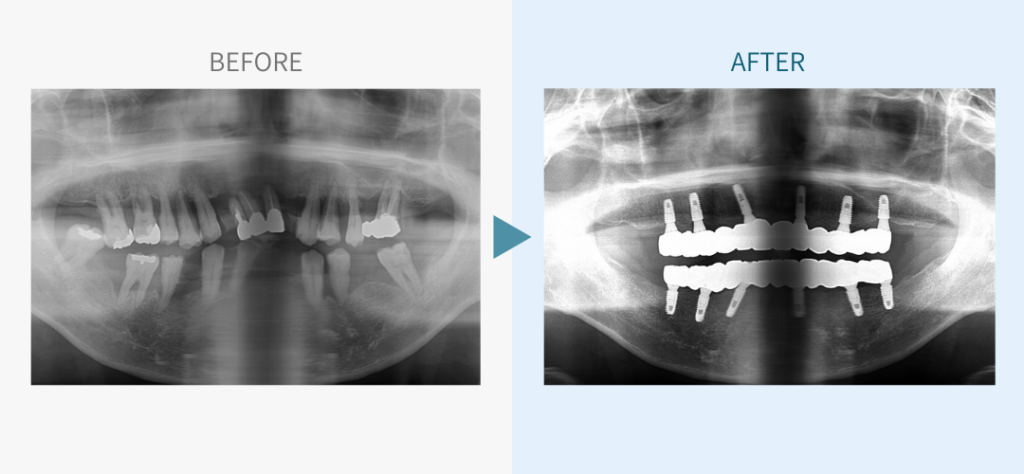

デンタルチームジャパンでは、サイナスリフト(上顎洞底挙上術)や骨造成など、他院で「骨が足りない」と断られた難症例にも対応しています。

こちらではその一部の症例についてご紹介します。